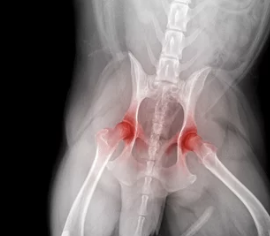

- 유전적 요인 (고관절 이형성증, 슬개골 탈구 등)

- 고관절 이형성증의 경우 교정 수술을 시행